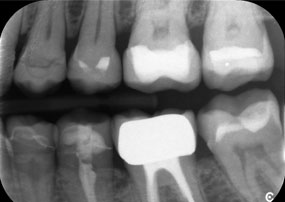

Рентгенова снимка на челюстта на 81-годишна пациентка.

Фигура 1: Естетична рехабилитация на металокерамични корони: Пълно отстраняване и подмяна на 40-годишни металокерамични корони за подобряване на естетиката при 81-годишна пациентка.

Предизвикателството беше да се премахнат дванадесет блок корони, изработени от сплав от неблагородни метали, без да се повредят подлежащите опорни зъби. Наконечникът беше използван за прецизно разрязване на керамичните слоеве и разделяне на металната конструкция с помощта на карбиден борер, което позволи минимално травматично отстраняване на короните. Само за 30 минути старите възстановявания бяха отстранени, което позволи подготовката на нова протеза, състояща се от циркониеви корони с пълна анатомична форма в задната част и фасети във фронталната зона. Резултатът беше цялостна реставрация, която осигури както функционален, така и естетичен успех (виж фиг. 1).